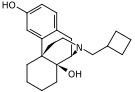

Oripavine derivatives

- Buprenorphine—partial agonist

- Dihydroetorphine

- Etorphine